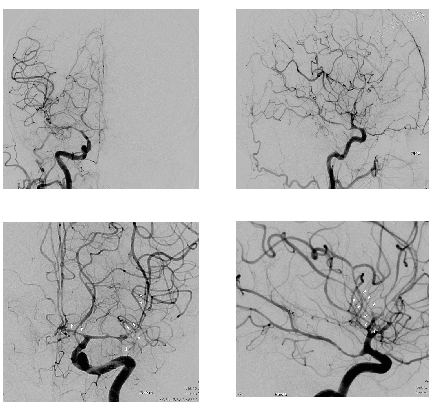

The serial angiographic images are depicted in figures 1 to 4. We can appreciate that over a period of 6 days in the anterior circulation the CVS has progressed from terminal ICA, and M1M2 segments and spreading distally over the arterial tree to involve the M3 M4, A3 A4 segments, and distal PCAs. Each time after lysis the spasm got relieved and when it recurred it did not appear in a segment in which it existed but was more pronounced distally in a new segment of the same vessel as if the vessel is getting squeezed distally. We call this phenomenon a "Marching Pattern".

Figure 1 1stepisode of CVS . Distal ICA,A1,M1,M2 and proximal PCOM in spasm, both sides.

Figure 2 2ndepisode of CVS-distal ICA snd proximal PCOM are normal, CVS involves M1A1.

Figure 3 3rdepisode of CVS. Proximal ICA,M1 looks normal.CVS seen in distal M2M3.

Figure 4 4thepisode of CVS. Involves the M3,M4 and A3,A4 segments.